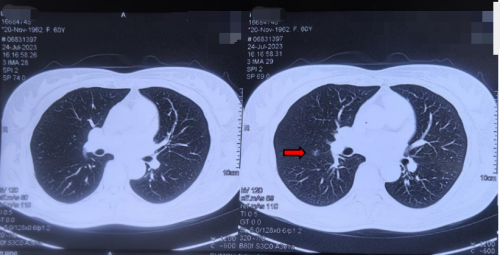

韩丹阳医生结合患者舌苔、脉象及体质辨识,辨证为“气滞血瘀证”,属中医“积聚类病”范畴。在继续遵循西医影像随访的基础上,韩医生为其开具了益气活血、化痰散结的中药复方,嘱咐她煎煮服用。

患者于2023-07-24外院定期复查肺CT影像图(3im29)